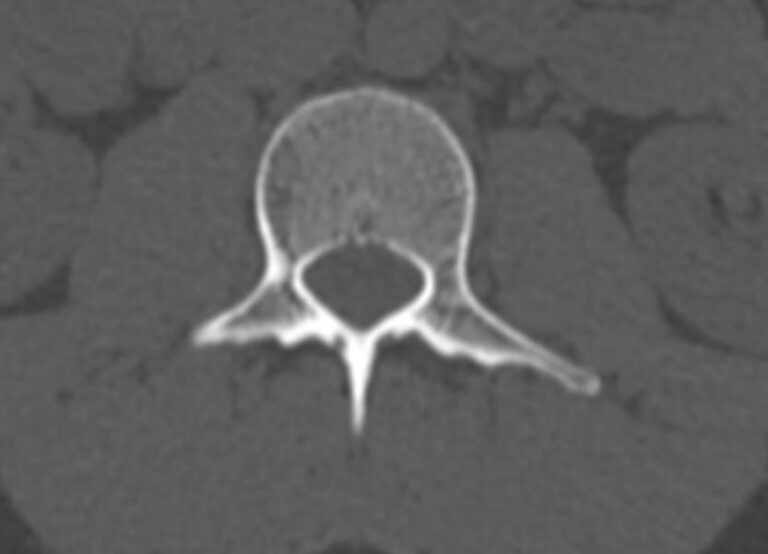

Для диагностики даже незначительных патологических изменений в различных отделах позвоночника, особенно в случае распространенного поражения, применяется один из современных наиболее информативных методов обследования – мультиспиральная компьютерная томография всего позвоночника. Методика основана на использовании проникающей способности рентгеновских лучей через органы и ткани человека и позволяет получить подробное изображение всех структур позвоночного столба. В комплексное обследование входит исследование шейного, грудного, пояснично-крестцового отделов позвоночника и копчика.

- дегенеративно-дистрофические заболевания позвоночника (остеоартроз, спондилез, деформирующий спондилоартроз);

- стеноз (сужение) позвоночного канала;

- грыжи межпозвонковых дисков (протрузии, экструзии и грыжи Шморля);